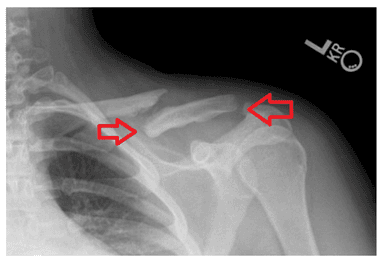

Xương đòn hay xương quai xanh là xương ở phần vai và ngực cấu thành, có vai trò trong sức mạnh vai – cánh tay và yếu tố thẩm mỹ. Gãy xương đòn là tình trạng chấn thương ở bộ phận này và thường gặp với đoạn 1/3 giữa. Những biểu hiện gãy xương đòn bao gồm:

Gãy xương đòn là tình trạng chấn thương ở bộ phận này và thường gặp với đoạn 1/3 giữa

Phẫu thuật gãy xương đòn là sử dụng các phương tiện để nối phần xương đã gãy về tình trạng ban đầu tạo điều kiện cho xương hồi phục. Phương pháp này áp dụng cho bệnh nhân với đường gãy quá mức phức tạp, gãy dài hoặc di lệch nhiều chồng ngắn trên 2cm đe dọa tổn thương mạch máu.

Phương pháp này được điều trị với: đóng đinh nội tủy hoặc KHX bằng nẹp vít. Để được chỉ định phương pháp phù hợp cần phụ thuộc vào nhiều yếu tố.